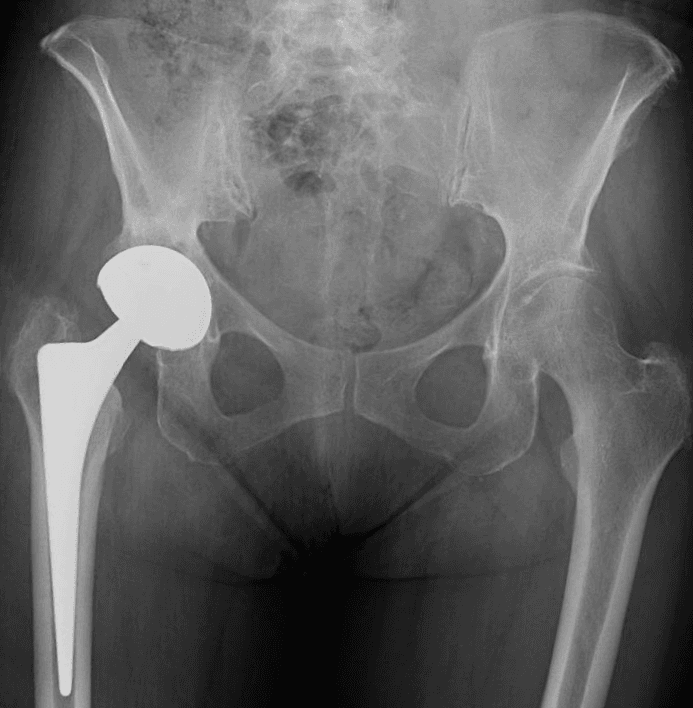

L’intervento di artroprotesi d’anca prevede la sostituzione dell’articolazione dell’anca mediante l’impianto di componenti protesiche in leghe metalliche, come il titanio, accoppiati a materiali plastici (polietilene di ultima generazione) e/o ceramiche. Questo processo include la sostituzione del femore prossimale (testa e collo) e il rivestimento della cavità acetabolare del bacino. L’obiettivo principale di questa procedura è ripristinare un’articolazione stabile e funzionale, migliorando significativamente la capacità di movimento del paziente, alleviando il dolore e migliorando la qualità della vita.

Esistono diverse vie d’accesso chirurgiche per l’artroplastica d’anca; quelle preferite nel nostro centro, a seconda delle caratteristiche del paziente, sono la via postero-laterale e la via anteriore. Ognuna di queste vie ha caratteristiche e vantaggi specifici, e la scelta è sempre basata sulle esigenze individuali del paziente.